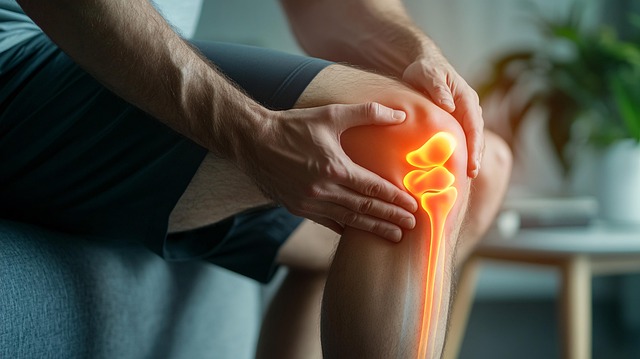

고관절은 허벅지뼈와 골반이 연결된 중요한 관절로, 걷기, 앉기, 서기 등 일상적인 움직임에 영향을 미칩니다. 이 관절은 우리의 일상생활에서 매우 중요한 역할을 하며, 나이, 무리한 운동, 외상, 관절염 등 여러 가지 요인으로 인해 통증이 발생할 수 있습니다.

고관절 통증은 단순히 불편함을 넘어 삶의 질에 큰 영향을 미칠 수 있으며, 방치하면 퇴행성 관절염을 비롯한 심각한 질환으로 악화될 가능성이 있습니다. 따라서 고관절의 건강을 유지하고 문제를 조기에 발견하는 것이 매우 중요합니다.

특히, 고관절은 신체의 중심부에 위치하여 체중을 지탱하고 이동을 돕는 역할을 하므로, 통증이 생기면 단순히 움직임에 불편함을 느끼는 것뿐만 아니라, 일상생활의 많은 부분에서 큰 어려움을 겪을 수 있습니다. 이로 인해 통증이 발생하면 조기에 적절한 대처가 이루어져야 합니다.